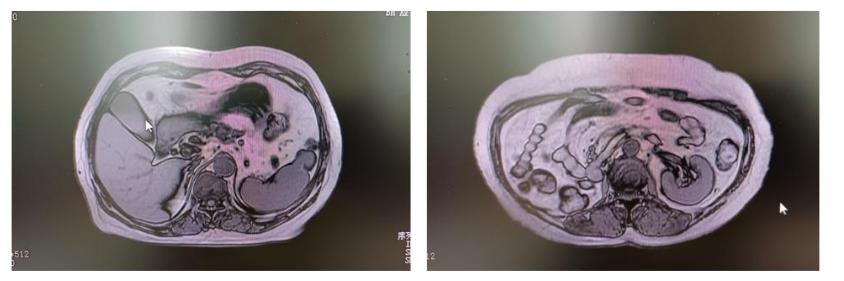

原则上所有局部肿瘤直径在以下实体癌都适用碘125粒子源治疗。瘤径 ≤ ,适合碘 125 粒子源植入治疗;瘤径 — ,周围转移卫星灶,慎行碘 125 粒子源植入。且适用于:肺癌、乳腺癌、食管癌;肝癌、直肠癌、前列腺癌、子宫颈癌、阴道癌、舌癌、鼻咽癌、上颌窦癌、腮腺癌、口咽癌、等及其转移的淋巴结、骨、器官转移灶等。

CT和超声引导下植入碘 125 粒子具有明显的优势:内照射剂量小,作用时间更长,治疗定位更准确,对肿瘤的局部作用均匀,辐射半径小 ( 约 ) ,对周围正常组织的损伤小。是一个较好的局部治疗措施。